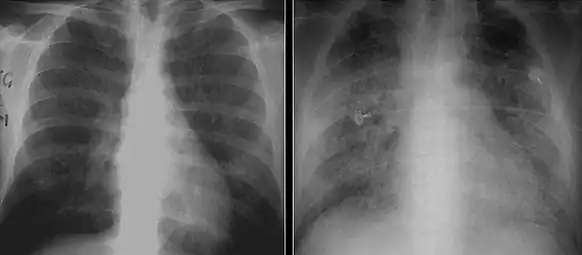

The diagnosis can be confirmed by the characteristic appearance of the chest X-ray and an arterial oxygen level that is strikingly lower than would be expected from symptoms. Gallium 67 scans are also useful in the diagnosis. They are abnormal in a high percent of cases and are often positive before the chest X-ray becomes abnormal. Chest X-ray typically shows widespread pulmonary infiltrates. CT scan may show pulmonary cysts[20] [2][21].